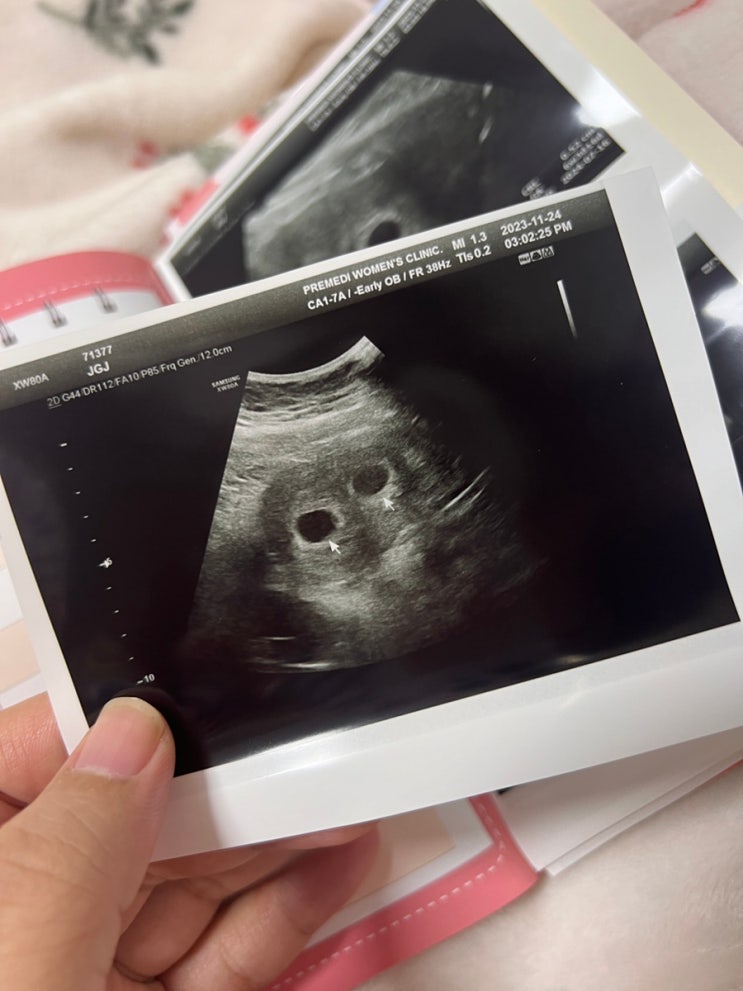

시험관 1차성공 / 프레메디 산부인과 시험관 쌍둥이 부정출혈 입덧시작

저번 글에선 분명 아기집이 하나였는데.. 음.. 그렇죠?? ㅋㅋㅋㅋㅋㅋㅋㅋㅋㅋㅋㅋ 시험관을 하고나서 5주 ...